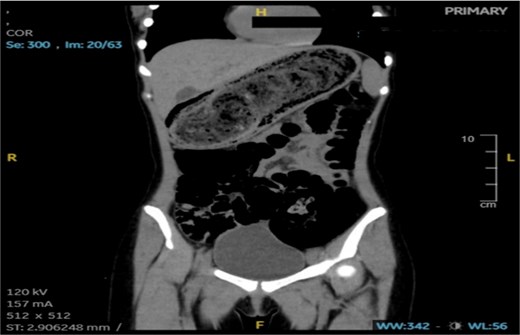

An abdominal CT scan showed a large, intragastric mass with a characteristic mottled appearance and gas entrapment (Figs 1 and 2), consistent with a trichobezoar. The mass extended into the duodenum, confirming the diagnosis of Rapunzel syndrome.

The patient was scheduled for exploratory laparotomy under general anesthesia. Intraoperatively, a large trichobezoar composed of hair and undigested food material was identified and removed via a gastrotomy. The mass measured ~22 × 7 × 8 cm and had a tail extending into the duodenum (Fig. 3). The stomach and intestinal wall were intact, with no evidence of ulceration or perforation. The postoperative course was uneventful, and the patient was started on intravenous fluids, antibiotics, and analgesics. Oral feeding was gradually resumed, and she was discharged in stable condition 5 days after surgery.

CT imaging played a crucial role in the diagnosis; the characteristic “mottled gas” appearance of the mass helped differentiate the trichobezoar from other gastric masses or tumors. Upper GI endoscopy can also be diagnostic and therapeutic in smaller cases, but large bezoars like the one described typically require surgical removal.